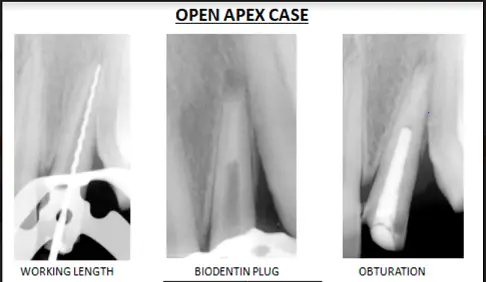

Management of Open Apex Under Dental Operating Microscope

The patient came with persistent pain in upper front tooth region post traumatic injury occurred 5 years back. On radiographic examination an open apex was spotted in relation to the upper lateral incisor. The working length was determined with apex locator. Biomechanical preparation was done with rotary file system and the open apex was closed under Dental Operating Microscope with the formation of biodentin plug. Pain was relieved and the patient was kept on follow up.